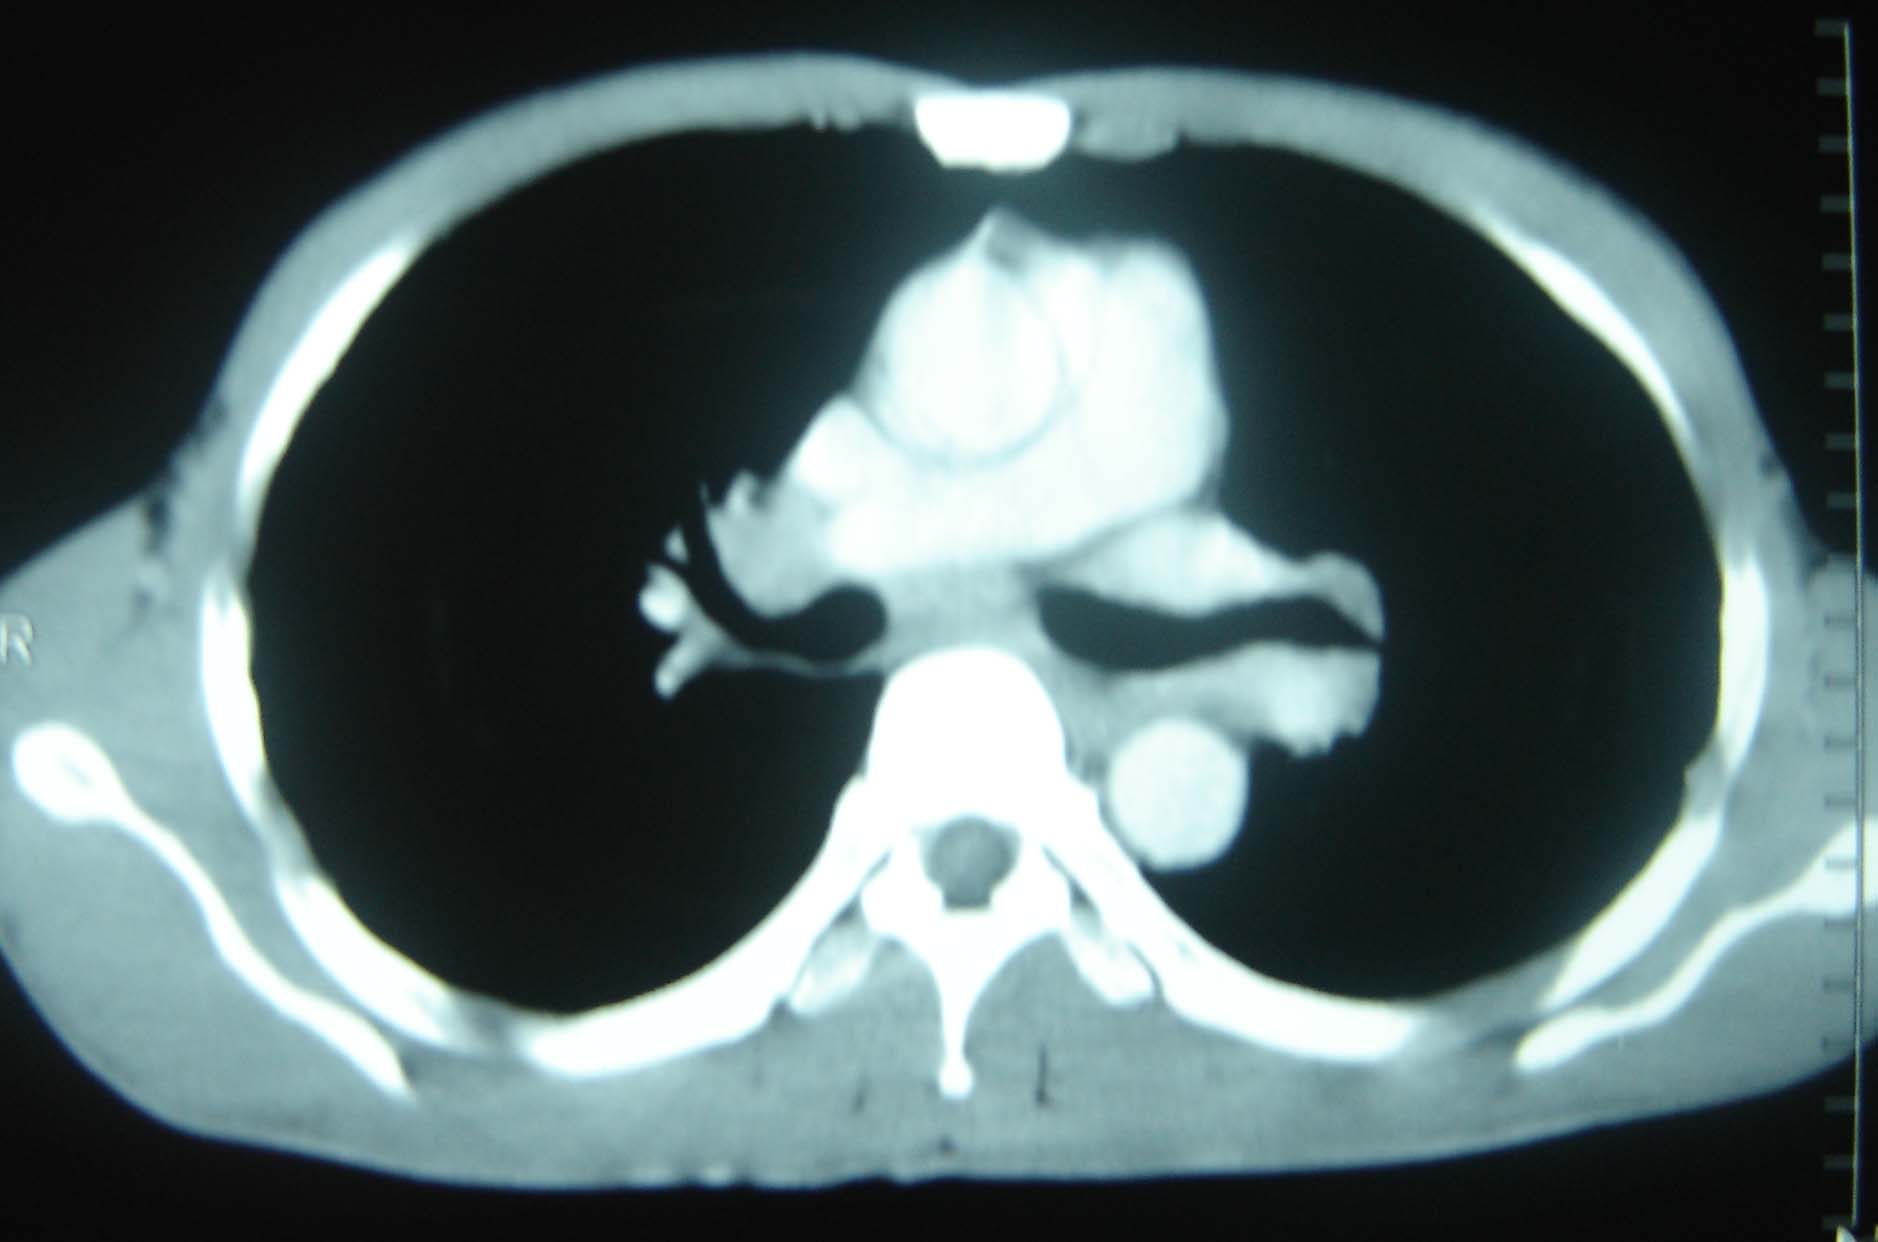

标题: CT25321:两肺多发结节 请会诊 [打印本页]

标题: CT25321:两肺多发结节 请会诊

男 、43岁,咳嗽胸痛,装修工,平时接触粉尘较多,有吸烟史10多年,纤维支气管镜检查未发现异常,胃镜、腹部b超检查亦未发现异常,颈部淋巴结活检未发现肿瘤细胞。

不能排除转移,如果不能找到原发灶,只有短期随访。

结节病?转移瘤?

1)考虑双肺及胸膜多发性转移瘤。2)肺气肿。